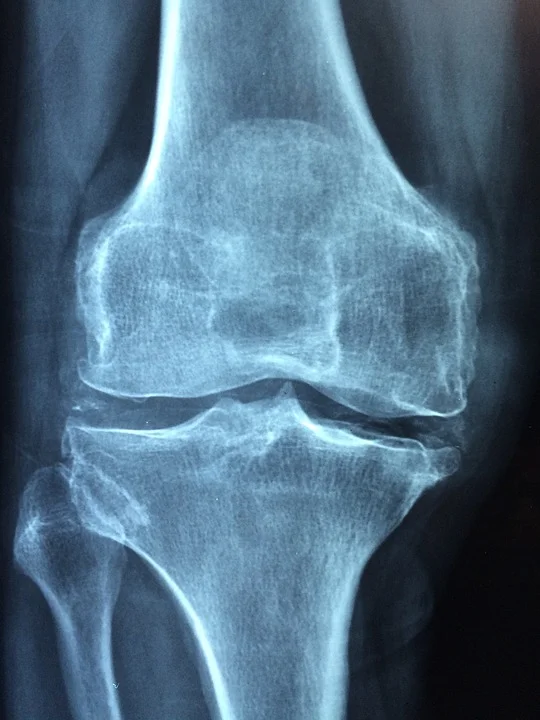

9. Supports Bone Health

Silibinin is a potential therapeutic agent for promoting bone-forming osteoblastogenesis and encumbering osteoclastic bone resorption. R

It does this possibly by sotpping tartrate-resistant acid phosphatase, Cathepsin K induction and MMP9 (matrix metalloproteinase-9) activiy. R

In animals:

- Milk thistle supported bone healing of mice by improving BMD (bone mineral density), seum levels of ALP (bone alkaline phophatase) and osteocalcin. R